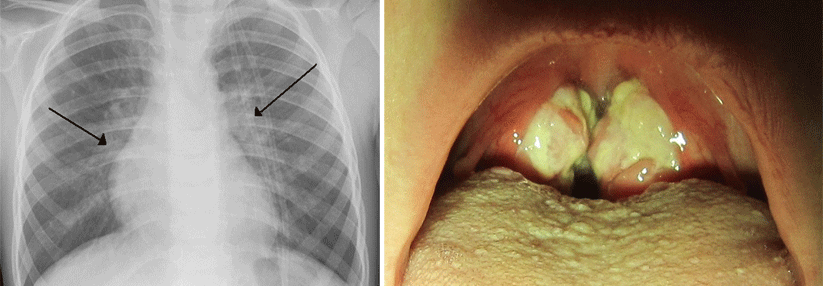

Wenn Patienten unter Luftnot leiden, gilt es abzuklären, ob ein Asthma, eine Fibrose, eine COPD oder das Herz dahinter stecken. Wenn Patienten unter Luftnot leiden, gilt es abzuklären, ob ein Asthma, eine Fibrose, eine COPD oder das Herz dahinter stecken. © Pixabay

Wenn Schmerz das häufigste Symptom darstellt, das Patienten zum Arzt treibt, folgt Atemnot wahrscheinlich an zweiter Stelle. Nur ist sie weit weniger gut beforscht und sperriger im Management: Wenn ein Patient Schmerzen äußert, fängt die Ursachenforschung dort an, wo es wehtut – wo bei Dyspnoe beginnen?

Erste diagnostischen Überlegungen: Herz und Lunge

Zwar würde man beim Herzinfarkt nicht an die Dyspnoe als Kardinalsymptom denken, aber eine niedrige Auswurfleistung kann über die periphere Minderdurchblutung einen Laktatanstieg auslösen, der seinerseits den Atemantrieb steigert, erklärte Professor Dr. F. Joachim Meyer, Chefarzt der Pneumologie und Pneumologischen Onkologie am Klinikum…